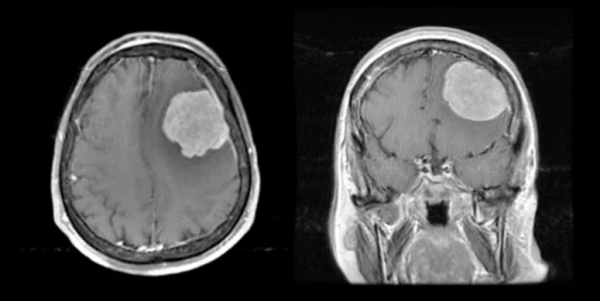

病例2

患者男,40歲,意外跌倒致頭部損傷,無意識喪失。頭部CT掃描顯示可疑腫塊,釓對比的T1加權MRI顯示左側凸面的硬腦膜病變,尺寸為4.5x4cm,並顯示了均勻的增強。腦膜瘤的T1加權磁共振成像(MRI)掃描,顯示軸向(左)和冠狀(右)檢視。

由於病灶較大且患者相對年輕,因此進行了開顱手術,將病灶全部切除。病理組織與世界衛生組織(WHO)的II級腦膜瘤一致。

腦膜瘤是臨床上最常見的原發性顱內腫瘤。根據WHO的分級,可被分為以下幾類:

➤I級腦膜瘤佔腦膜瘤的80-85%,是低級別良性腫瘤,無進展生存率高,總死亡率低。

➤儘管進行了最大限度的手術和放療,但Il級(非典型)和I級(間變性)腦膜瘤的複發率較高。